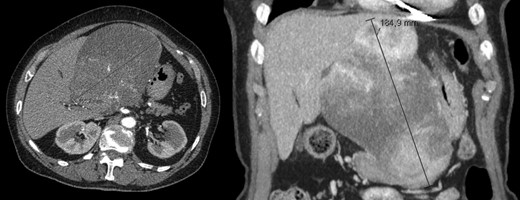

A 26-year-old woman, with past medical history of removal of hemangiopericytoma of the right leg, was referred to our Hepatobiliary Unit due to a liver tumor that was discovered on abdominal-pelvic computed tomography (CT) scan, performed after complaints of epigastric pain. CT scan (Fig. 1) showed a voluminous, heterogeneous, hypervascular mass, occupying segments 4, 5 and 8, with 19 cm in diameter, as well as suspicious lesion on left iliac bone suggestive of solitary fibrous tumor metastasis.

Abdomino-pelvic computed tomography (AP-CT) – voluminous heterogeneous liver mass in segments 4, 5 and 8 with 19 cm in diameter.